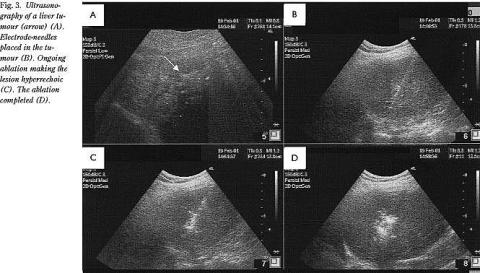

Ved RF-behandlingen anvender man to elektroder, og behandlingen fungerer i princippet som elektrokoagulation. Den ene elektrode er den uisolerede spids af en 14 gauge nål, der placeres i den tumor, som ønskes destrueret. Den anden elektrode er en stor, flad elektrode (neutralelektroden), som sættes på patientens lår. En generator skaber en strøm mellem de to elektroder (Fig. 1 ). Der anvendes vekselstrøm med en frekvens i området 450-500 kHz. Deraf navnet radiofrekvens, da frekvensen svarer til frekvensen for radiobølger. Ved denne frekvens er den elektriske modstand i kroppen relativt lille, og der kan derfor genereres stor strømtæthed omkring RF-nålen, og der afsættes betydelig varme. Ved opvarmning over 45°C fremkaldes proteindenaturering og celledød. Der tilstræbes opvarmning til over 60°C. For at opnå størst mulig udbredelse af varmeenergien er det vigtigt at undgå forkulning, da ledningsevnen i vævet ellers hæmmes betydeligt. For at undgå dette kan man anvende en kølet nål. Dette opnås vha. cirkulerende vand i tynde skyllekanaler i nålen (cooled needle ) (11). Der er desuden indbygget temperaturføler i nålen, så opvarmningen kan styres. En anden, og nu meget anvendt metode, RITA, er at anvende multiple elektroder og temperaturfølere (op til ni), som kan føres ud af RF-nålens spids, når denne er anbragt i tumoren (Fig. 1 og Fig. 2 ).

RF-nålen kan indføres UL-vejledt i tumoren perkutant, vha. laparoskop eller ved åben kirurgi. Den perkutane behandling foretages i generel anæstesi. Hver ablation af et 4-5 cm i diameter stort vævsområde tager 10-30 minutter. Når RF-nålen retraheres øges strømstyrken, så nålestikkanalen koaguleres for at undgå udsæd af tumorceller. Den perkutane teknik anvendes ved tumorer, der er op til 4 cm i diameter og er lokaliseret, så RF-nålen UL-vejledt kan indføres i tumoren (Fig. 2, Fig. 3 ). Større tumorer kræver derfor flere overlappende nåleapplikationer. Laparoskopisk RF-behandling anvendes nu ved overfladisk beliggende tumorer, som kan være vanskelige at erkende tilstrækkeligt godt visuelt ved perkutan UL-scanning (Fig. 4 ). Åben RF-behandling udføres evt. samtidig med resektion af resecerbare tumorer, hvor ikkeresecerbare tumorer RF-behandles. Man kan da samtidig foretage inflow -okklusion af levergennemblødningen med tang på ligamentum hepatoduodenale (Pringles manøvre). Herved kan kølevirkningen af levergennemblødningen mindskes, så et større tumorrumfang kan opvarmes og destrueres. Samtidig kan tumorer, der er tæt på større blodkar, specielt v. portae og v. hepatica, bedre behandles.